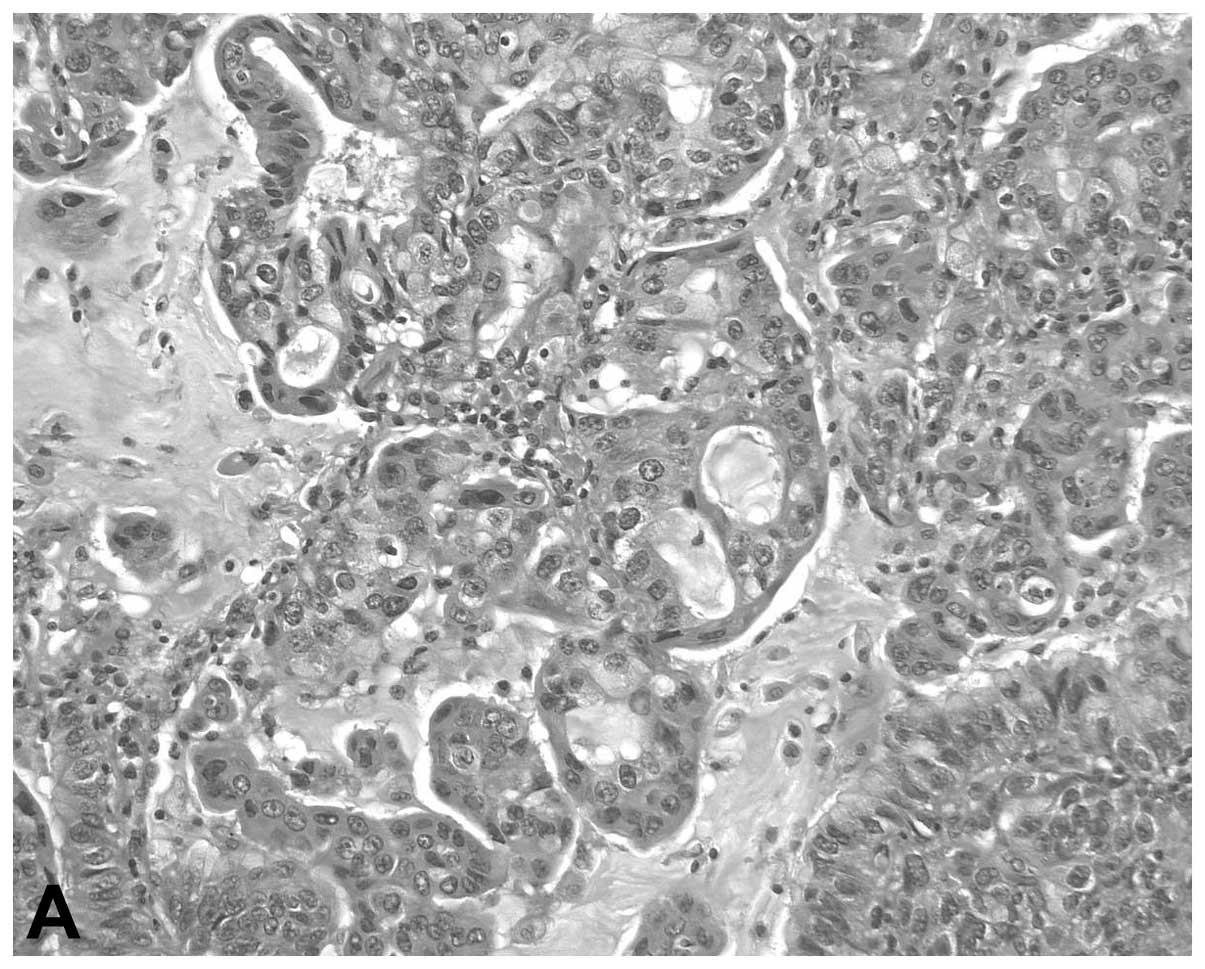

Adenosquamous cell lung cancer successfully treated with gefitinib: A case report

Although adenosquamous cell lung cancer (ASCLC) is included in the non‑small‑cell lung cancers (NSCLCs), the number of currently available studies on the response of this type of cancer to epidermal growth factor receptor‑tyrosine kinase inhibitors (EGFR‑TKIs) is limited. This is the case report of a 66‑year‑old female who was referred to the Mito Medical Center (Mito, Japan) with hemoptysis and the chest computed tomography (CT) scan revealed a large cavitary mass in the lower lobe of the left lung. The patient underwent surgical resection of the lesion and the final pathological diagnosis was ASCLC staged as pT2bN2M0. Notably, an EGFR exon 19 deletion was identified in the adenocarcinomatous as well as the squamous cell carcinomatous components of the tumor. Despite adjuvant chemotherapy, the patient developed small cavitary metastases in the lungs bilaterally. Therefore, treatment with gefitinib was initiated. The chest CT scan revealed substantial regression of the metastatic cavitary tumors in both lungs, with thinning of the walls. The patient remains alive and recurrence‑free 19 months following the initiation of gefitinib therapy. This case demonstrated an optimal clinical response to gefitinib treatment for EGFR mutation‑positive ASCLC, suggesting that gefitinib is a therapeutic option for such a subset of patients with ASCLC.

Figure 1